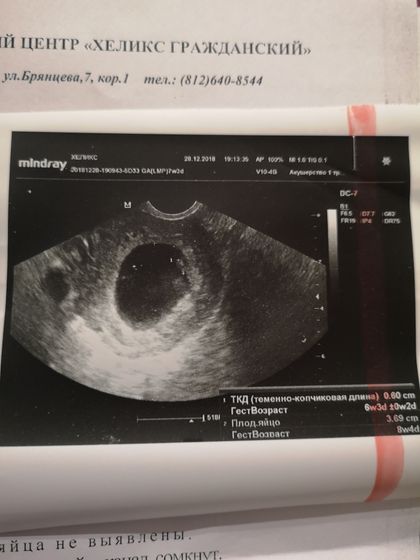

плодное яйцо, и что этоплохо, но почему, отказалась объяснять, типа зачем меня расстраивать перед НГ? сердцебиение послушать не дала, вроде как вредно (тоже странно), но чётко показала, что сердце бьется… В общем, у кого подобное было? Что делать? Прикладываю фото, почитайте пожалуйста

У вас вытянутое плодное яйцо+ гипертонус… а это угроза.С малышом все хорошо, но нужно сохранять беременность… попейте нош-пу и свечи папаверин+ дюфастон.мне назначали 3 раза в день и то и то… но лучше конечно идите к врачу скорее...

Только деформация плодного яйца.

Но это от тонуса матки. Свечки с папаверином делайте.